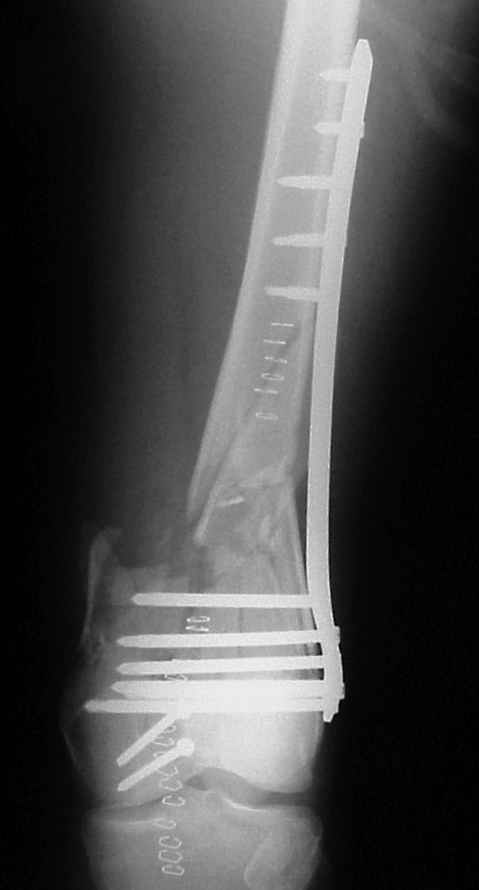

On Thersday afternoon he was alright, he is a very active man and he was moving well both knees. Later that evening he told me that while he was a little bit asleep he turned on the bed and felt pain and that the femur was loose. Here are the X-rays we took.

In this case, the fixation might have failed because of inadequate purchase of the side plate to the shaft. I say this because the initial lateral xray shows that the plate seems to be fairly anterior to the mid-axis of the femoral shaft. Once the plate pulled off of the shaft, it continued to pull out of the distal segment. With the short unicortical screws used for shaft fixation, it is imperative that the plate be applied precisely at the midline (widest diameter) of the femur. If it is applied even slightly anterior or posterior to the midline, the screws just don¹t engage the cortex. You can¹t tell by feel, since the screws lock firmly into the plate.

Considering that even with the plate in place there was significant malalignment, with the such revision the wrong axis would remain the same.

Condyles have separated. Would separate (peripheral ? 3.5mm, lag screws, medial to lateral or lateral to medial outside LISS footprint) lag screws have been helpful? Intercondylar fracture needs open reduction and good interfragmentary compression.

LISS is a bit proximal, and screws are not parallel with joint line. Is there excessive valgus on appropriate AP views? You might want to check the mechanical axis using electrocautery cord stretched across knee, from center of femoral head to middle of talus.